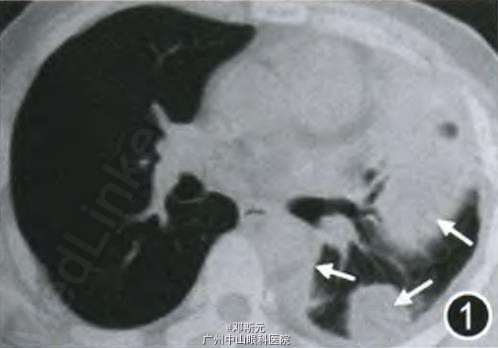

患者男,40岁,因“胸痛4个月”于2013年7月收入北京协和医院呼吸科。2013年3月患者无诱因出现双侧胸痛,呈持续性隐痛,与呼吸相关。胸部CT示右肺上叶小结节,左侧胸膜明显增厚及左肺下叶膨胀不全,左侧胸腔积液(图l,2),PET—CT示右肺上叶结节放射性摄取稍高,标准摄取值(SUV)为1.1,左侧胸膜多发结节状放射性摄取增高灶,SUV值为2.9,中下肺为著。胸腔穿刺抽出血性胸腔积液,为渗出性,未见癌细胞。2013年4月行“胸腔镜辅助右上肺结节切除术”,术后病理为“右上肺错构瘤(以软骨成分为主)”。但术后胸痛未缓解,且左侧胸痛加剧,复查胸部CT提示左侧胸腔积液增多。2013年6月行“左侧小开胸、粘连松解及胸膜病变切除活检术”,术中见胸膜结节状增厚并广泛粘连,胸膜腔闭锁,切取局部少许胸膜送检。术后病理示纤维脂肪组织,局灶轻度异型细胞增生;免疫组织化学染色细胞角蛋白AEI/AE3阳性,考虑间皮瘤不除外,未明确诊断。2013年7月行“经皮左侧胸膜穿刺活检术”,术后病理(结合患者上次开胸胸膜活检标本)示肿瘤细胞排列成小巢状,短索状,可见血管腔样裂隙,基质呈浅蓝色黏液透明样。肿瘤细胞呈上皮样或组织细胞样,圆形、多边形或梭形,胞质丰富,嗜伊红色,胞质内管腔或空泡形成不明显,瘤细胞核略呈空泡状,核仁及核异型性不明显,未见明确的核分裂相,未见实性梭形细胞区域或坏死。免疫组织化学染色示分化簇3l、分化簇34及波形蛋白阳性,第八因子相关抗原、CK5/6及钙视网膜蛋白阴性。符合EHE(图3~,为进一步治疗收入院。有长期吸烟史。